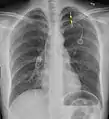

الأشعة السينية على الصدر

عادة ما يكون التصوير الشعاعي العادي للصدر، بإشعاع الأشعة السينية من الخلف (من الخلف للأمام) هو أنسب فحص في البداية. وعادة ما يتم تنفيذ ذلك خلال الشهيق (مع كتم النَفَس). لأن التصوير بالأشعة السينية أثناء الزفير (بعد خروج الهواء) لا يعطي أي معلومات إضافية.[12][13] إذا لم تُظهر الأشعة السينية الساقطة من الخلف للأمام استرواح صدري، ولكن كان هناك شكوك قوية في وجوده، يتم عمل أشعة سينية جانبية ( بإسقاط الأشعة من الجانب)، ولكن هذه ليست الطريقة الروتينية.[13][17] ومن المألوف وجود انحراف المنصف (التركيب بين الرئتين التي يحتوي على القلب، والأوعية الدموية الكبيرة، والممرات الهوائية الكبيرة) بعيدا عن الرئة المتضررة بسبب اختلافات الضغط. لذا فإن هذا الانحراف ليس دليلا على حدوث استرواح الصدر الضاغط، إنما يتحدد أساسا عن طريق مجموعة من الأعراض بالإضافة إلى نقص الأكسجين، والصدمة.[12]

يمكن تحديد حجم استرواح الصدر (أي حجم الهواء في الفضاء الجنبي) بدرجة معقولة من الدقة عن طريق قياس المسافة بين جدار الصدر والرئة، ويتم على أساسه تحديد العلاج، لأنه يتم التعامل مع وجود استرواح صدري أصغر بشكل مختلف. وجود طبقة رقيقة من الهواء حجمها 2 سم يعني أن استرواح الصدر يحتل حوالي 50٪ من نصف الصدر.[13] وقد ذكرت المبادئ التوجيهية المهنية البريطانية أن القياس يجب أن يتم على مستوى باب الرئة (مكان دخول الأوعية الدموية والمسالك الهوائية في الرئة) باعتبار 2سم كنقطة فاصلة،[13] في حين تنص المبادئ التوجيهية الأمريكية أن القياس ينبغي أن يتم من قمة الرئة مع التفريق بين استرواح الصدر "الصغير" و "الكبير" بفاصل 3سم.[23] ولكن قد تبالغ الطريقة الأخيرة في حجم استرواح الصدر إذا كان يقع أساسا في القمة، وهو أمر شائع.[13] الروابط بين طرق القياس المختلفة ضعيفة، ولكن هي أفضل الطرق المتاحة السهلة لتقدير حجم استرواح الصدر.[13][17] يمكن أن يساعد المسح المقطعي (انظر أدناه) في تحديد حجم استرواح الصدر بدقة أكبر، ولكن لا يوصى باستخدامه الروتيني مع هذه الحالات.[23]